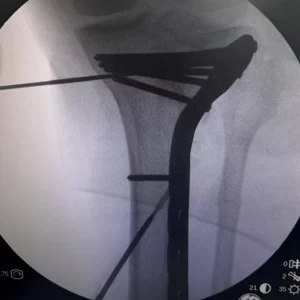

Placa INNOBLOX

Sistema 3.5

Palo de Golf

Indicaciones

Fracturas en cara lateral de la tibia proximal con compromiso

intra y extra articular.